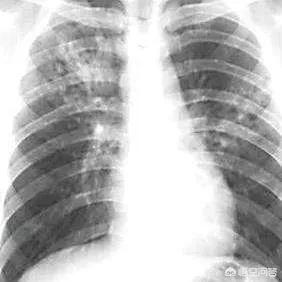

1. la tuberculose

En 2015, environ 390 000 personnes vivant avec le VIH sont mortes de la tuberculose. La tuberculose est la première cause de mortalité chez les personnes vivant avec le VIH en Afrique et la première cause de mortalité chez les personnes vivant avec le VIH dans le monde. Les symptômes comprennent la fièvre, les sueurs nocturnes, la toux, les expectorations, etc.

- TB

La tuberculose peut survenir en même temps que le SIDA ou avant le SIDA. Au stade avancé du sida, l'immunité est détruite et les bacilles tuberculeux latents deviennent actifs, provoquant la tuberculose. Les principales manifestations cliniques sont les suivantes : fièvre, toux, expectorations, hémoptysie, sueurs nocturnes, amaigrissement et perte d'appétit. Selon des statistiques approximatives, 15 % des personnes infectées par le VIH peuvent développer une tuberculose.